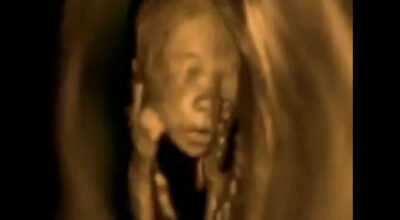

Después de haber visto en ecografías 3D cómo son los movimientos del feto, incluso las pataditas que a veces son demasiado fuertes y provocan pequeños bultitos en la tripa de las mamás. Ahora hemos sido testigos una vez más de las impresionantes imágenes de un feto pero esta vez campando a sus anchas en el vientre de su madre.

De forma nítida en el vídeo que te mostramos a continuación podrás ver cuáles son los movimientos que suelen hacer los fetos dentro de la tripa de la madre así como sus posturas más comunes y por decirlo de alguna manera, cómo es su vida ahí dentro durante los 9 meses que tienen que estar allí.

Somos capaces de distinguir su carita, nariz, manos, brazos… Incluso vemos cómo el cordón umbilical que le une a la madre se ve claramente rodeándole. ¿No te parece algo impresionante? ¡Aquí tienes el vídeo para que puedas verlo con tus propios ojos!